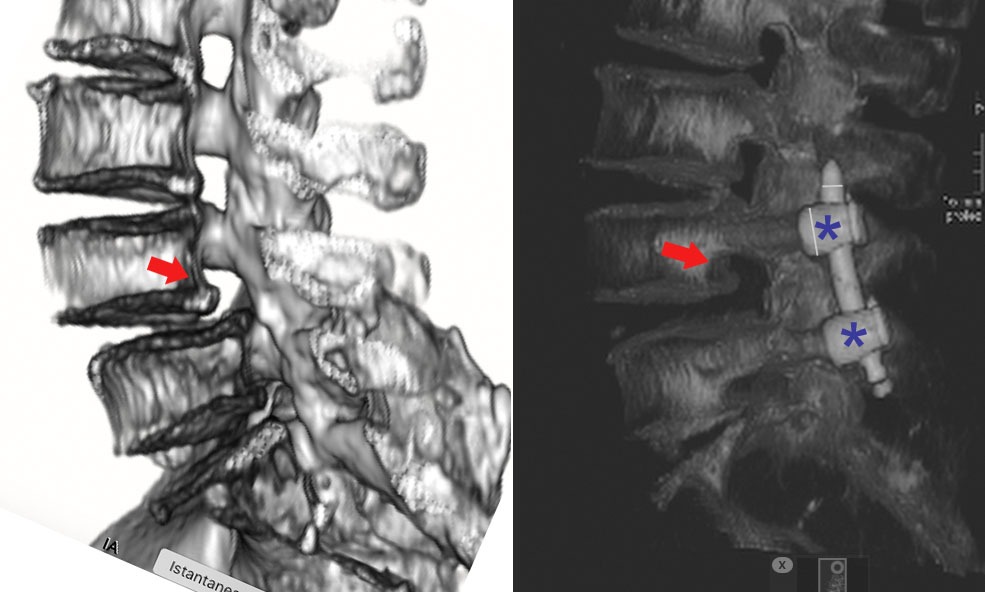

La spondilolisi è una frattura da stress dell’istmo vertebrale, una piccola porzione dell’arco osseo posteriore della vertebra. Si tratta di una condizione subdola perché spesso asintomatica, ma che può evolvere in spondilolistesi, una problematica più seria caratterizzata dallo scivolamento vertebrale.

Diagnosi: RX e Risonanza Magnetica per una Conferma Certa

RX in proiezione obliqua: utile per identificare il tipico “Doggy’s Collar Sign”.

Risonanza Magnetica (RMN): permette di evidenziare le fasi iniziali della patologia con maggiore precisione.